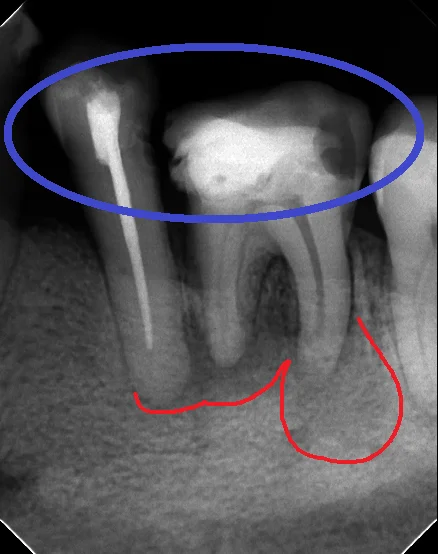

中心結節破折が原因で起こった神経の壊死を放置して、外部吸収が起こったケース

中心結節破折が原因で起こった神経の壊死を放置して、外部吸収が起こったケース

メタルコアによる歯根破折

こんにちは。 今日は表題の通り、歯根破折についてです。 歯根破折というのは読んで字のごとく、歯の根の部分である「歯根」が折れてしまった状態を表します。 折れる方向やその深さによっては抜歯に直結する非常に危険なものです。 歯根破折は色々な原因…

続きを読む →